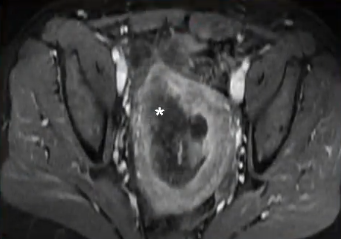

![]() |

| 47 岁女性,伴有 严重经期出血和盆腔疼痛症状。冠状位[A]和矢状位[B]的 T2 加权磁共振成像显示子宫增大范围内存在中等信号病变。[C] 轴位 T1 后处理图像显示子宫内有强化肿块,边缘不规则。 | ||

影像学检查结果: 质地较硬的肿块,边缘不规则,T2 期呈中等至较高强度,T1 期呈高信号(提示出血) 没有任何标准能够将退化的子宫肌瘤与平滑肌肉瘤区分开来。